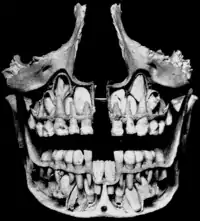

Молочні зуби

Молочні зуби, також дитячі, тимчасові зуби — перший набір зубів у діфіодонтних ссавців, включаючи людей.

Молочні зуби у людей прорізуються після народження в певній послідовності. Однойменні зуби на кожній половині щелепи прорізуються одночасно. Зазвичай, нижні зуби прорізуються раніше верхніх. Молочний прикус ділять на два періоди. У першому періоді (з моменту формування до 3,5 років) зуби розташовані щільно без проміжків, стертість зубів непомітна — прикус ортогнатичний в силу відставання росту нижньої щелепи і витягування її вперед. У другому періоді (3,5 — 6 років) у процесі росту щелеп формуються фізіологічні проміжки між зубами (діастеми або треми), перехід від ортогнатичного прикусу у прямий, ознаки значної стертості зубів.